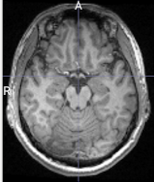

3D brain image에 대해 n4 bias field correction을 적용해보았을때의 모습이다(왼쪽 : original, 오른쪽 : processed). 자세히 살펴보면 original data에서의 low frequency를 갖는 region들이 향상이 된 부분을 볼 수 있다. (그림의 A 부분 참고)